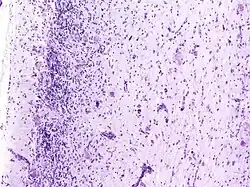

Pathologie und Histopathologie

Nach der WHO-Klassifikation der Tumoren des zentralen Nervensystems zählt es zu den Grad I Tumoren. Das Syndrom zeigt allerdings gleichzeitig Charakteristika einer gutartigen Neubildung und einer Fehlbildung, so dass die genaue Einordnung noch unklar ist. Auch ob es sich um ein Hamartom handeln könnte, ist in Fachkreisen umstritten.

Auf zellulärer Ebene sieht man dysplastische (hypertrophe und später blasig aufgetriebene, vakuolisierte) Purkinjezellen. Die Schichtung des Kleinhirns ist umgekehrt (invertiert) und die Körnerzellschicht ist weitgehend aufgelöst.